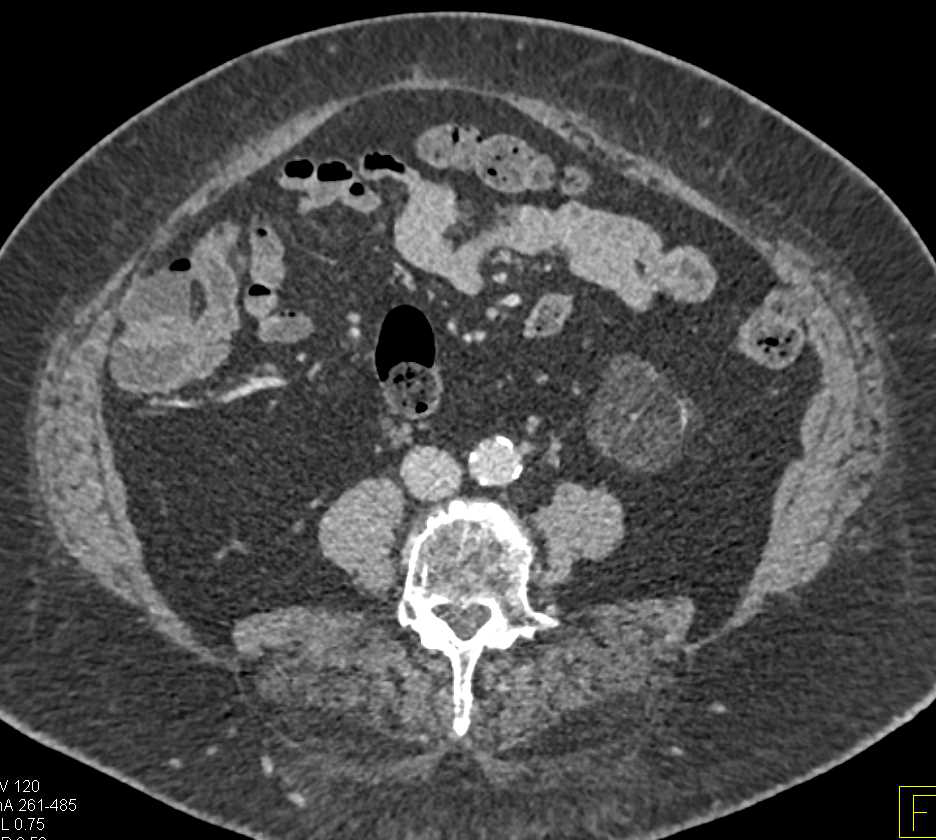

Post Ablation Changes Left Kidney